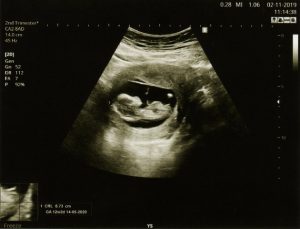

- The sex can usually be determined by ultrasound from the 16th to 20th week, depending on the position of the baby and the quality of the image.